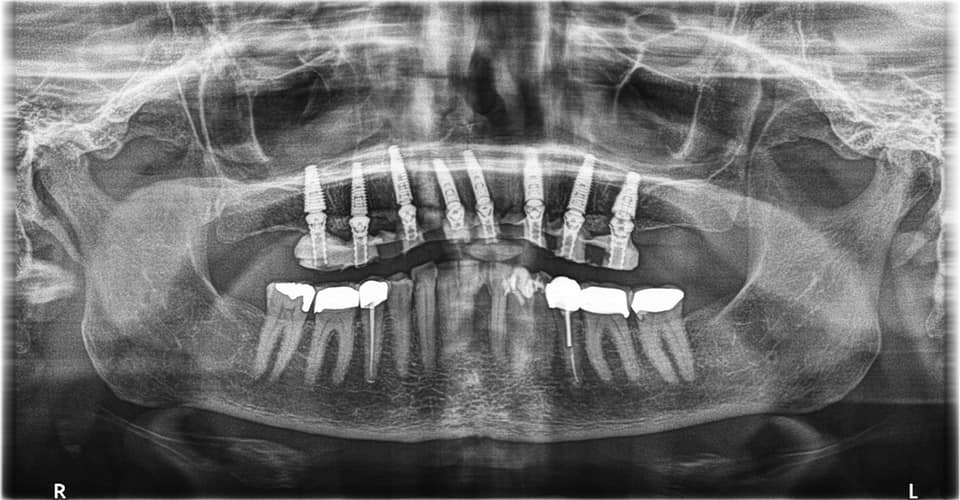

Below is a case of full arch same day temporization using the socket shield , root submergence and pontic shield techniques to preserve the site architecture . Neodent GM implants were placed in a guided fashion and same day temporization was performed using a milled PMMA.

The final bridge was constructed in monlithic zirconia.